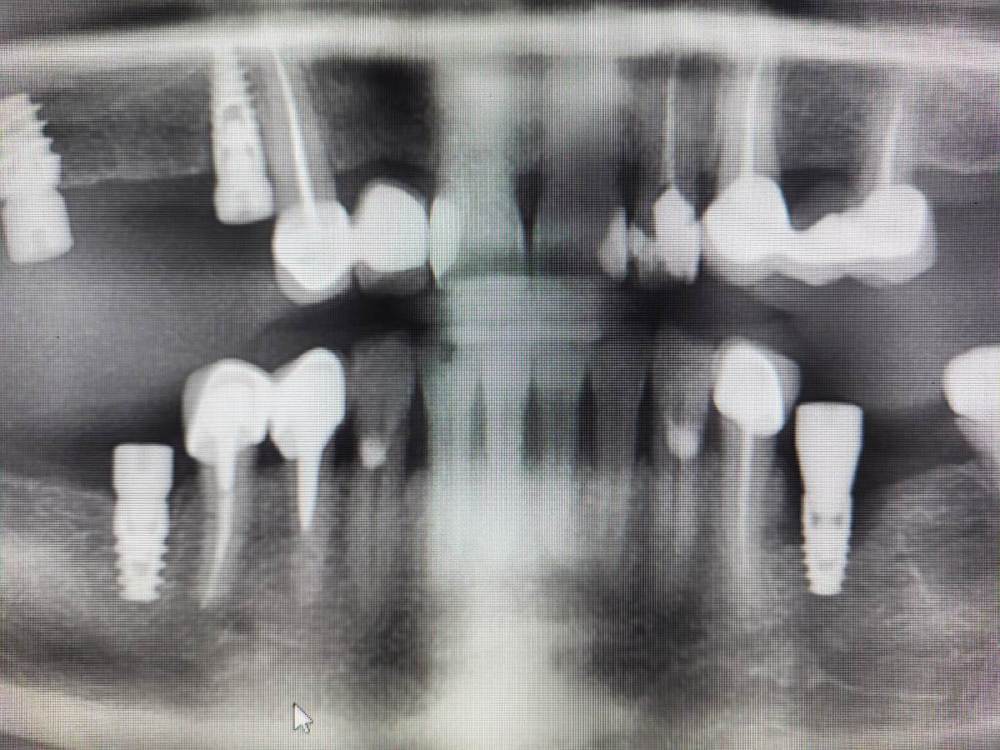

Irouil Опубликовано 28 ноября, 2023 Поделиться Опубликовано 28 ноября, 2023 Дорогие коллеги, прошу советов и мнений Пациентка 52 лет, соматика без особенностей В мае 2023 установлен имплант в позицию 3.5, первый срез КТ - на момент установки. В августе был утерян ФДМ, установил другой, снимок на момент обращения с незначительной резорбцией В ноябре пациентка пришла протезироваться, у винта выраженная щелевидная резорбция язычно и кратерообразная - параплатформенно Три других винта, установленных в то же время (но без головняка с ФДМ) выглядят более чем удовлетворительно Что скажете? P.S. поперечный срез КТ выставлен на уровне платформы импланта Ссылка на комментарий